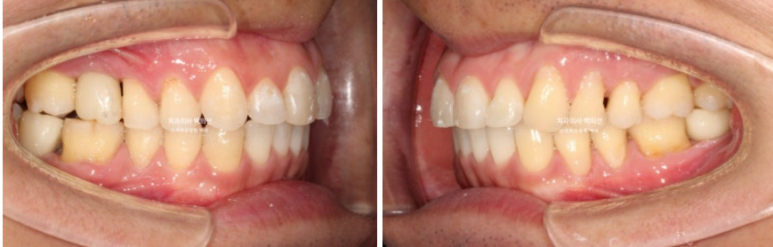

24.05~25.03